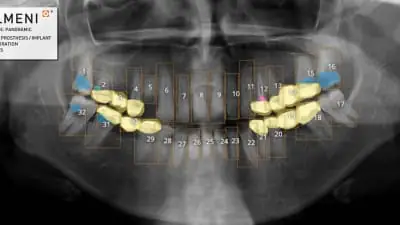

VELMENI for DENTISTS (V4D) assists dentists in the detection of dental caries, fillings/restorations, fixed prostheses, and implants in digital bitewing, periapical, and panoramic radiographs of permanent teeth in patients 15 years of age or older.

VELMENI is the first dental AI approved by the FDA to detect pathologies in panoramic X-Rays. VELMENI for DENTISTS adds its US FDA clearance to existing Canadian MDEL and New Zealand MEDSAFE clearances.

Many dental conditions are difficult to see in dental X-Rays. The VELMENI AI reveals numerous pathologies, increasing diagnostic accuracy.

Pictured: VELMENI-PAN-Findings